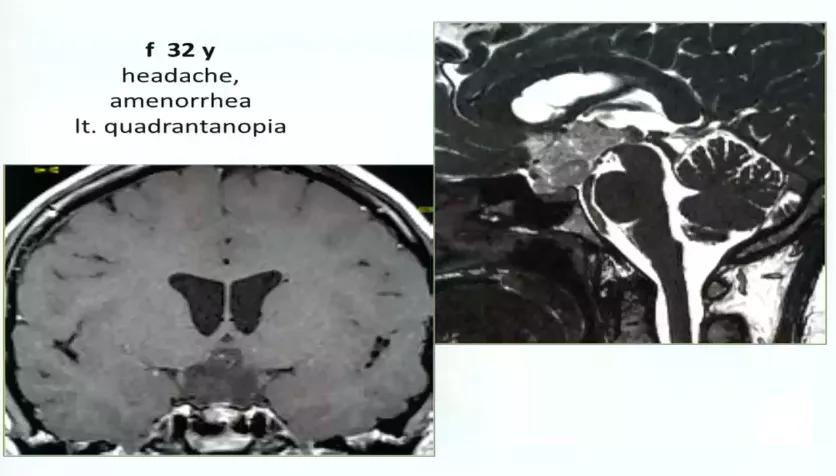

32岁女性,头疼、闭经、视野缺损,左侧视野象限盲,累及视路后部、下丘脑,脚前窝。病变完全位于中线,因此采用前纵裂入路。手术最终安全全切。

图:术前MRI

术中情况: 病变完全位于中线入路,因此采取前纵裂入路。

术后情况: 手术做的非常漂亮,解剖性全切,无神经损伤。